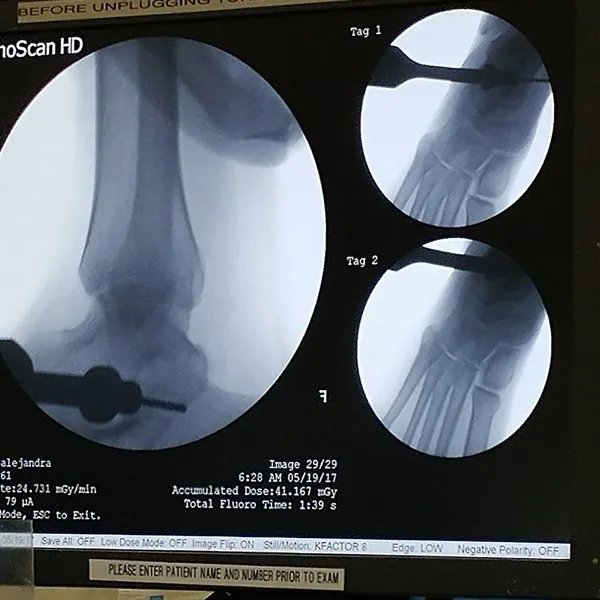

See What's Going on Inside Our Podiatrist's Office

With 32 years of experience, Dr. Daniel Brandwein DPM, PA, FACFAS is your trusted choice for podiatric care in the Pompano Beach, FL area. Take a look at the photos below to see what's happening inside our locally and family owned clinic. To find out how we can help with your foot care needs, please contact us today.